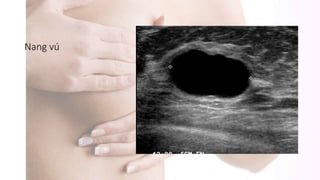

Siêu âm

Nang vú